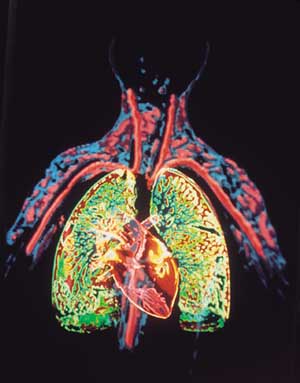

القلب Heart عضو عضلي يضخ الدم في جسم الإنسان. ومع كل دقّة يدفع القلب الدم الضروري للحياة عبر جسم الإنسان. ويحمل الدم الأكسجين والغذاء لكل خلايا الجسم وتبدأ دقات القلب ذات الإيقاع المنتظم قبل سبعة أشهر من ميلاد الطفل تقريبًا. وعندما يتوقف القلب تتوقف الحياة، إلا إذا ساعدت أجهزة آلية خاصة على دوران وأكسجة الدم. والقلب عضو عضلي مجوّف كبير، ينقسم إلى مضختين متجاورتين. وتنقل الأوردة الدموية الدم في جميع أنحاء الجسم إلى المضخة الواقعة في الجهة اليمنى التي ترسله بدورها إلى الرئتين لحمل الأكسجين، ومن ثم، ينساب الدم المؤكسد إلى الجهة اليسرى من القلب التي تضخه إلى أجزاء الجسم المختلفة بوساطة الشرايين. وهناك صمامات تتحكم في سريان الدم داخل القلب. والمضخة اليسرى، التي تدفع الدم إلى جميع أنحاء الجسم أقوى وأكبر حجمًا من المضخة اليمنى. والقلب والتشكيلات الأنبوبية الأخرى مثل الشرايين والأوردة والشعيرات تسمى جميعًا الجهاز الدوري أو الجهاز القلبي الوعائي. ينظم الجهاز العصبي عمل القلب وأجزاء أخرى من الجهاز الدوري. وينظم الجهاز العصبي التلقائي، وهو جزء من الجهاز العصبي، ضربات القلب (النبض)، فيقللها أو يزيدها حسب حاجة الجسم؛ لذلك فإن القلب يدق بصورة هادئة مثلاً عندما يكون الإنسان نائمًا ويزود الجسم بكمية قليلة نسبياً من الأكسجين. وقد تزداد سرعة ضربات القلب مرة أخرى لتزيد كمية مردود الأكسجين للجسم بغزارة. ويحدث هذا عندما يزاول الإنسان التمارين الرياضية أو عندما يصاب بالخوف أو عندما يحتاج للمقاومة أو العراك أو الجري. وقد يصيب المرض أو الخلل أي جزء من أجزاء القلب أو الأوعية الدموية، ويعتبر ذلك من الأسباب الرئيسية للوفاة في البلدان الصناعية. وأكثر أمراض القلب شيوعًا هي التي تصيب الشرايين التي تغذي القلب نفسه بالدم. والخلل الذي يصيب هذه الشرايين قد يتطور مع سنوات عمر الإنسان. فترسُّب المواد الدهنية مثلاً، يؤدي إلى انسداد شرياني وإلى قلة كمية الدم التي تزود القلب. وإذا استقبلت عضلة القلب كمية قليلة من الدم فإن هذا قد يؤثر في أدائها أو إلى موتها. ويسمى هذا الخلل أو التلف الناتج من قلة إمداد عضلة القلب بالدم النوبة القلبية. والنوبة القلبية الخفيفة قد تجبر الإنسان لكي يعيش حياة أقل نشاطًا وحركة. أما النوبة القلبية القاسية أو العنيفة فتجعل القلب غير قادر على إمداد الجسم بكمية كافية من الدم، حتى في حالة الراحة الكاملة، وقد تؤدي إلى الوفاة. وقد تصيب الأمراض أجزاء أُخرى من القلب وقد يؤدي هذا إلى تأثير مدمّر مشابه. تحققت أهم التطورات الطبية الحديثة في مجال طب القلب، وهو حقل طبي يعنى بالأمراض التي تصيب القلب والأوعية الدموية. ومنذ آلاف السنين، لم يكن مرضى القلب يعرفون أصلاً أن لهم هذه المشكلة. وفي التسعينيات من القرن العشرين الميلادي، تعلم الأطباء كيف يشخصون ويعالجون بعض حالات مرض القلب التي كان علاجها علاجها مستحيلاً في السابق، وكانت تعني الوفاة لمن يصاب بها. وأدّى اكتشاف الأدوية والتطور الهائل في الجراحة إلى إعطاء عدد من مرضى القلب أملاً في الحياة، وبدأ الأطباء بزراعة القلوب بل طوّروا أجهزة تقوم بعمل القلب مؤقتًا. واليوم تُجرى كثير من الأبحاث في علم القلب ووظائفه، ويتم التركيز على دراسة الأسباب التي تؤدي إلى أمراض القلب حتى يمكن تفاديها. وتدرس أبحاث أخرى إمكانية خفض حالات الموت والعجز التي تنتج من أمراض القلب، عن طريق دعم وتطوير أدوية وعقاقير معالجة جديدة واستحداث قلب صناعي فعّال. هذه المقالة عن قلب الإنسان بصورة خاصة، والجزء الأخير منها يصف قلب الحشرات والسمك والطيور والحيوانات الأخرى. ولمزيد من المعلومات عن عمل الدم في الجسم،

تشكل العضلة القلبية النسيج الفعال وظيفيا من القلب حيث يؤمن تقلصها انتقال الدم وضخه من القلب إلى باقي الأعضاء مما يجعل القلب محطة الضخ الرئيسية للدم من القلب إلى العضاء لتزويدها بالأكسجين المحمل في الدم القادم من الرئتين, من ثم يقوم القلب بضخ الدم القادم من العضاء والمحمل بثاني أكسيد الكربون إلى الرئتين لتنقيته و تحميله من جديد بالأكسجين.

يحتوي الدم الذي يدخل الجانب الأيمن من القلب على ثاني أكسيد الكربون، وهو غاز فاسد تفرزه الخلايا والأنسجة في عملية إنتاج الطاقة. ويدخل الدم الأذين الأيمن عن طريق الوريد الأجوف العلوي والوريد الأجوف السفلي. وعندما يمتلئ الأذين ينقبض، ضاخًا الدم في البطين. وحينما يمتلئ البطين فإن الضغط المتولد يجعل الصمام المثلث الشرف ينغلق، والصمام الرئوي المؤدي للشريان الرئوي ينفتح، وبعدها ينقبض البطين ويدفع الدم في الشريان الرئوي ثم إلى الرئتين. وفي الرئتين يستبدل الأكسجين بثاني أكسيد الكربون. ثم ينساب الدم المؤكسد في الأوردة الرئوية للجزء الشمالي من القلب. انظر: الرئة.

ضخ الدم لكل أجزاء الجسم

يدخل الدم المؤكسد من الرئتين ويملأ الأذين الأيسر، ومن ثم ينقبض الأذين ليضخ الدم عبر الصمام التاجي في البطين الأيسر. وبعد أن يمتلئ البطين بالدم ينغلق الصمام التاجي وينفتح صمام الأبهر. ويتدفق الدم في الأبهر ويتوزع عن طريق الشرايين إلى خلايا وأنسجة الجسم المختلفة.